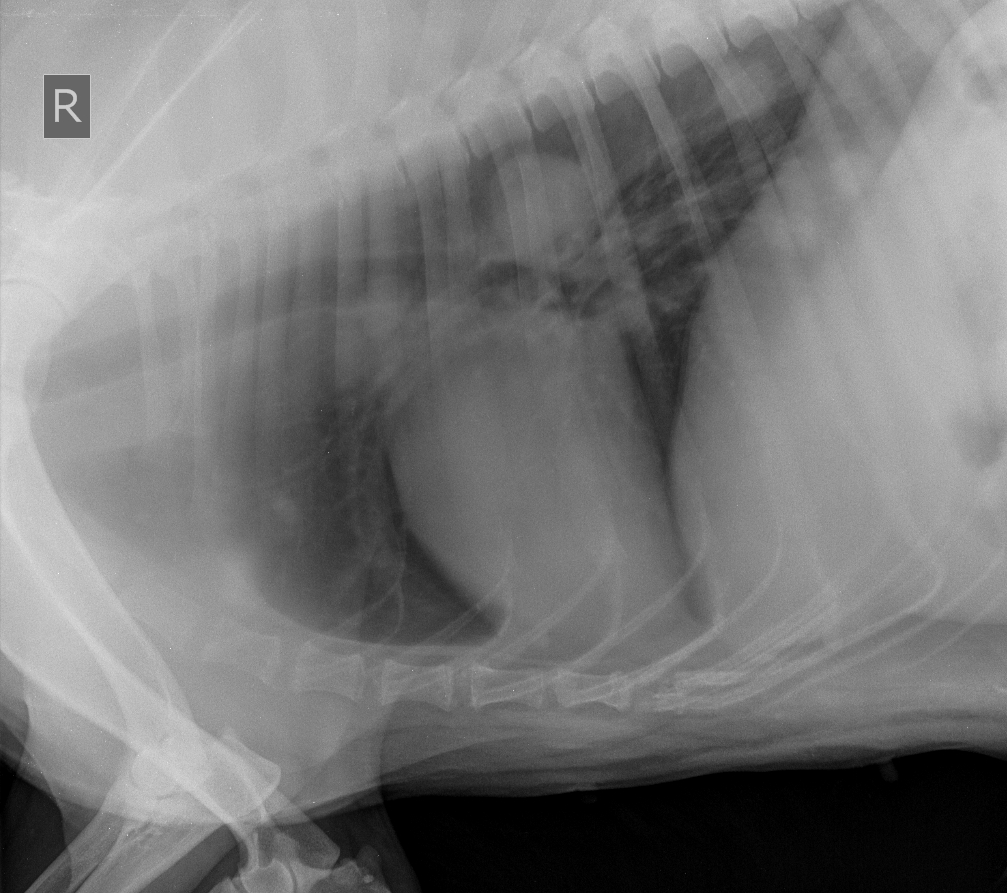

Собака, 9 лет, метастазы в легких